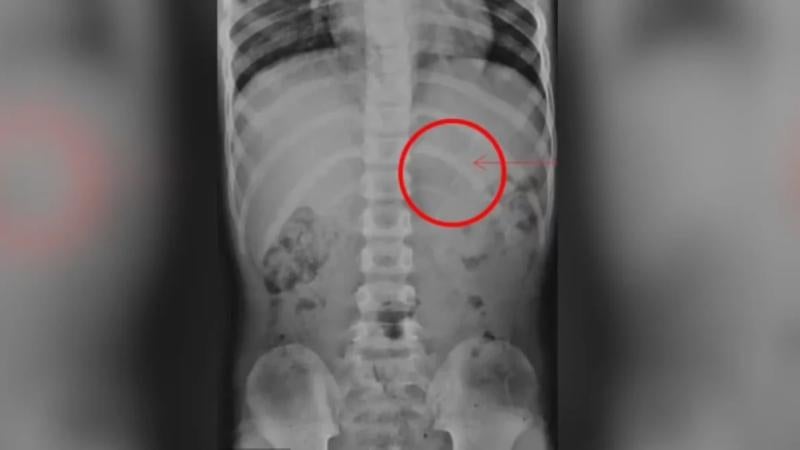

«La radiografía abdominal inmediata reveló un lápiz en el estómago con una longitud estimada de aproximadamente 10 cm y sin signos de complicaciones», asegura el informe.

Del mismo modo, las examinaciones no arrojaron signos de posible obstrucción, perforación o peritonitis en las continuas radiografías realizadas.